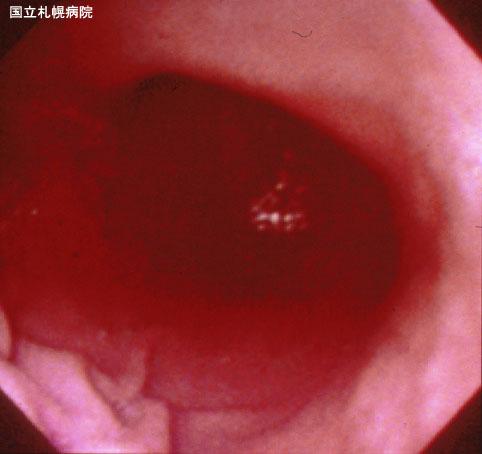

A case of an inflammatory tumor presenting as a gastric submucosal tumor.

[ Image ID:3325 ]

Inflammatory or ulcerative disease / lesions/Others

Stomach/Body

Endoscopy

40 -